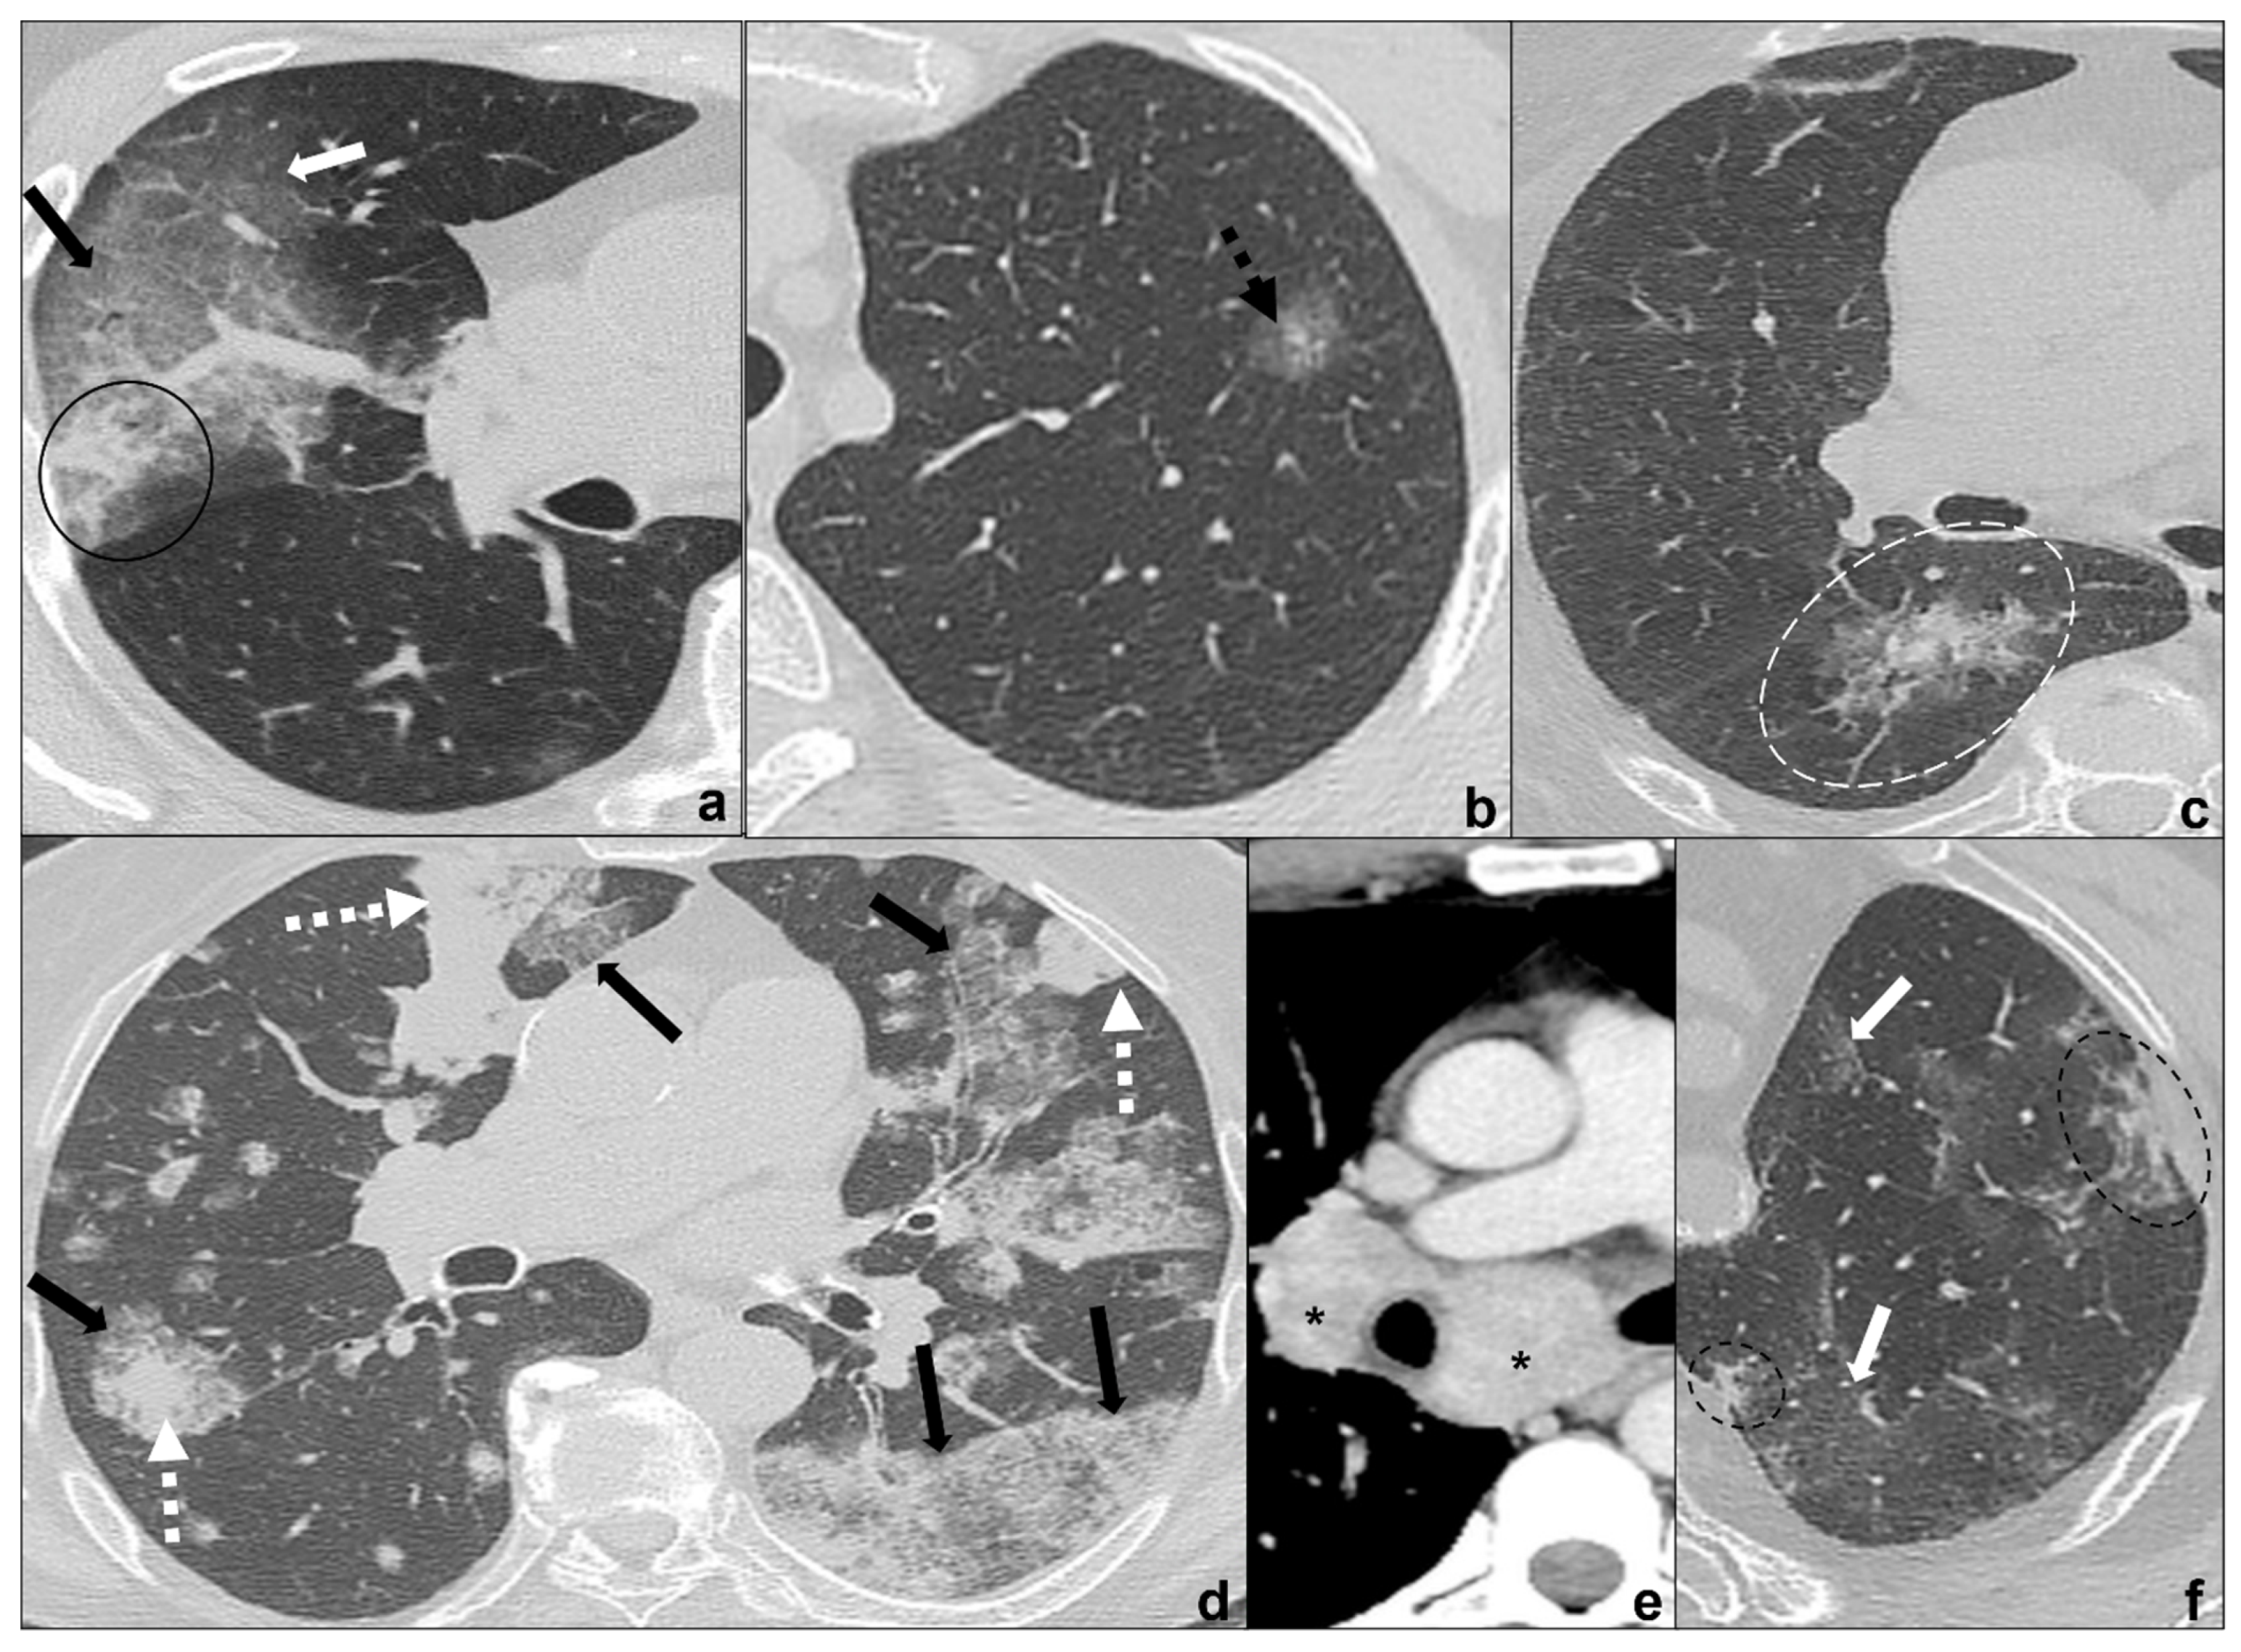

Anamnesis and clinical signs and symptoms are crucial for the suspect of solid lung tumors. Radiological features for differential diagnosis of a single consolidation and COVID-19 pneumonia [18,34,46,47,48] (Figure 5a–d):

Figure 5.

(a–e) Chest CTs showing differential diagnoses of COVID-19 pneumonia stage 3/consolidations. Subpleural ill-defined consolidations are typical of COVID-19 pneumonia stage 3 (black circle) and are generally easy distinguishable from lung cancer, especially if lung tumors present as big masses with spiculated margins, pleural retraction striae (dotted black circle in (b)), cavitations (black arrow in (b)) and lymphadenopathies (black asterisk in (c)). Contrast administration is useful to appreciate the inhomogeneous enhancement of lung tumor and mediastinal tissue infiltration (white arrow in (c)), and/or additional findings such as lobar atelectasis (dotted white arrow in (d)) secondary to bronchial invasion with progressive lobar hypoventilation and secretive stagnation. Solid metastases (e) may be differentiated by COVID-19 consolidations because they appear as roundish nodules with regular margins and a random distribution in relation to hematogenous spread. Lungs: mean window with 1500 HU; mean window level −600. Mediastinum: mean window with 350 HU; mean window level 50 HU.

- generally focal entities, appearing as a single nodule (<3 cm) or mass (>3 cm) with invasive and infiltrative features;

- spiculated margins with pleural and parenchymal retraction stripes causing extensive pulmonary distortions and mediastinal attraction;

- inhomogeneous density in relation to hemorrhagic and/or necrotic foci (e.g., small cell carcinoma, large cell carcinoma);

- inhomogeneous contrast enhancement that is typical of cancer and is not seen in COVID-19 consolidations;

- possible endobronchial growth and spread through airspace (STAS), which has been recognized as a feature with prognostic significance in 2021 WHO classification of thoracic tumors;

- not generally associated with ground-glass or crazy paving areas. If ground-glass or crazy paving areas are present due to edema and hemorrhage, they do not follow COVID-19 pneumonia phases;

- may be central or peripheral, but do not present a strictly subpleural distribution (squamous cell carcinoma and small cell carcinoma being generally central tumors whilst large cell carcinoma being often peripheral);

- grow during antibiotics/anti-inflammatory therapies;

- cysts and/or cavitations (squamous cell carcinoma);

- chest wall, mediastinum and mediastinal organs invasion (frequent in small cell carcinoma, which is most common oncological cause of superior vena cava compressive/infiltrative/thrombotic obstruction);

- associated findings such as atelectasis (Figure 5d) and post-obstructive pneumonia (typical of endobronchial growing tumors such as squamous cell carcinoma;

- lymphangitis carcinomatosis;

- mediastinal lymphadenopathies and pleural effusions;

- systemic metastasis, which are particularly early and frequent in small cell carcinoma.

Metastases are multiple parenchymal and/or pleural lesions secondary to a primitive cancer. Solid metastases present as solid, homogenous nodules with random distribution, regular margins, and nodular morphology, even if there are rarer and atypical presentations [37,38,49].

Anamnesis and clinical signs and symptoms are crucial for the suspicion of solid lung tumors. Radiological features for differential diagnosis of multiple consolidations and COVID-19 pneumonia [38,39,49] (Figure 5a,e):

- generally present as discrete regular nodules with roundish morphology while COVID-19 consolidations present ill-defined margins and do not show a nodular appearance;

- generally present a random distribution in case of hematogenous spreading or may present a spreading through airspace (STAS);

- may be asymptomatic and increase in number and dimensions during antibiotic and anti-inflammatory treatment;

- are not frequently associated with ground-glass or crazy paving opacities and do not follow COVID-19 pneumonia phases.

Although COVID-19 pneumonia may be an incidental diagnosis in asymptomatic patients [15], acute symptoms worsening and changing should always suggest an overlapping pathology or a progression and require urgent investigation (Figure 7a–d).

Figure 7.

(a–d) Chest CT of an oncologic patient affected by a paramediastinal lung cancer located in the apical segment of the right upper lobe (dotted white arrow) and undergoing chemotherapy and radiotherapy. After admission to the first aid with ageusia, anosmia, and fever, a chest CT scan was performed showing subpleural areas of ground-glass (white arrow in (b)) and crazy paving (black arrow in (c)) with the typical reversed halo sign or atoll sign (dotted black arrow in (d)), parenchymal consolidations (black circle in (a)) and subpleural parenchymal bands together with crazy paving opacities (black-bordered white arrow in (d)). Lungs: mean window with 1500 HU; mean window level −600. Mediastinum: mean window with 350 HU; mean window level 50 HU.